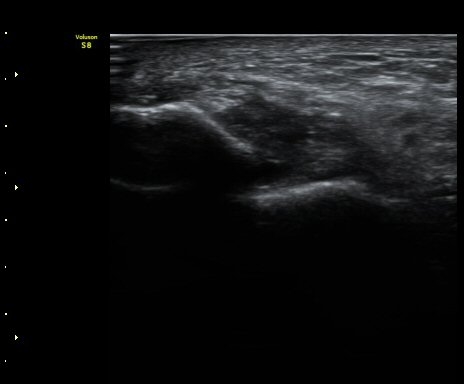

¹ß¸ñ ¾Õ Á¾´Ü¸é°Ë»ç¿¡¼­ ¹ß¸ñ°üÀý ³» ¼ö¾×Àú·ù°¡ °üÂûµÈ´Ù(±×¸² 1).